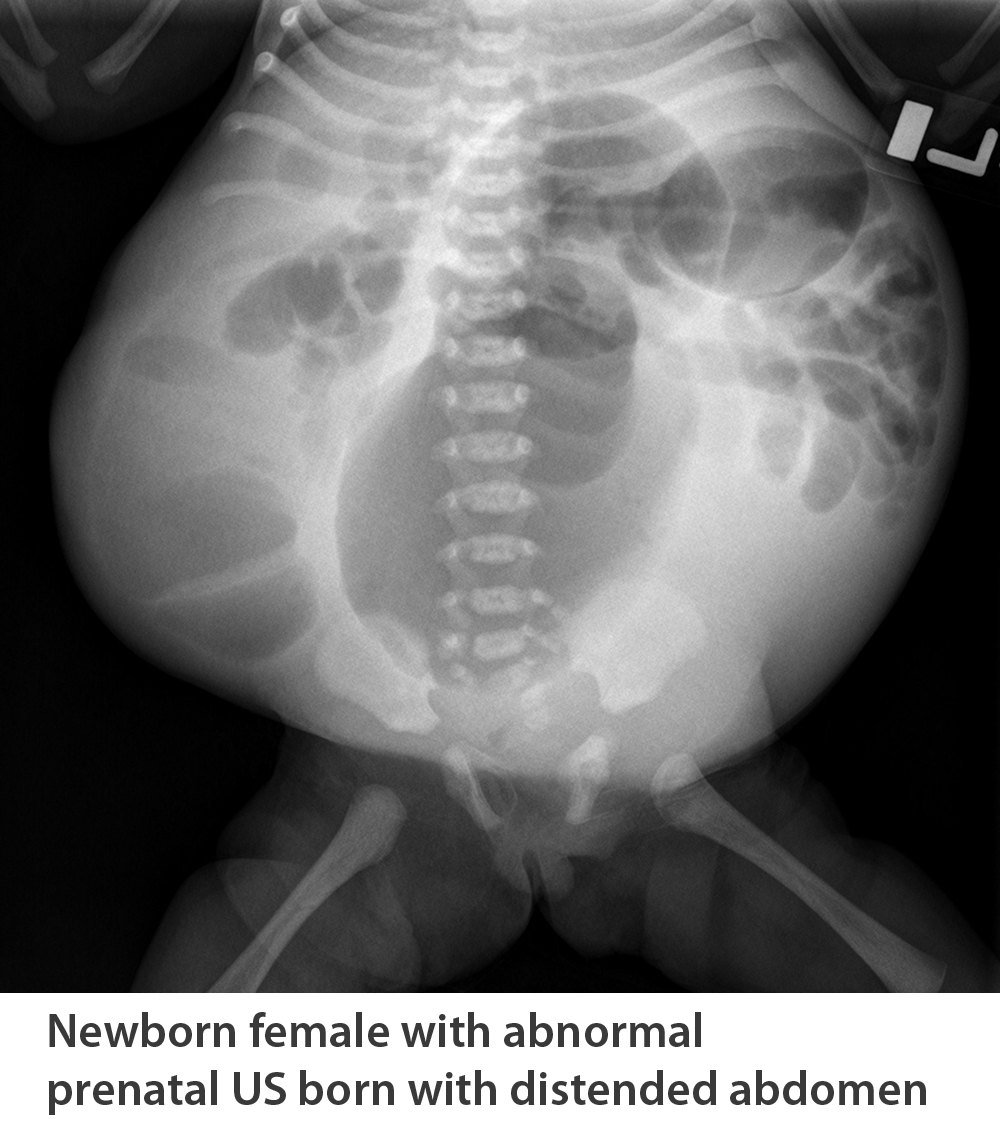

Kidney, ureter, and bladder (KUB) test findings can usually be used for diagnosis based on the typical appearance of the bowels hanging over the lateral edge of the abdominal wall. Enlarged bladder